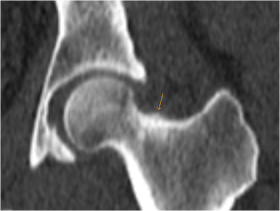

Osteoid Osteoma Radiology